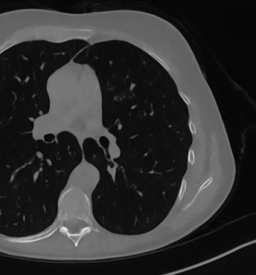

We now consider the P180,60subscript𝑃18060P_{180,60} CT protocol whose results are reported in Figure 6. In this case, the tomographic reconstruction is more challenging than in the previous experiment. The starting image xRISsubscript𝑥𝑅𝐼𝑆x_{RIS} has evident streaking artifacts and blur and some details are lost, especially in the first zoom. The artifacts are reduced in the xISsubscript𝑥𝐼𝑆x_{IS} (top right image), where some details are recovered and the edges are quite neat. The xINGsubscript𝑥𝐼𝑁𝐺x_{ING} image obtained with the proposed RISING (bottom right) is visually an excellent reconstruction. It is very similar to the xLPPsubscript𝑥𝐿𝑃𝑃x_{LPP} image, whose training, we remark, is based on more informative target images.

Refer to caption

Figure 6: Results on a test image from the Mayo data set, under the P180,60subscript𝑃18060P_{180,60} CT protocol. Top-left: xRISsubscript𝑥𝑅𝐼𝑆x_{RIS}; top-right: xISsubscript𝑥𝐼𝑆x_{IS}; bottom-left: xLPPsubscript𝑥𝐿𝑃𝑃x_{LPP}; bottom-right: xINGsubscript𝑥𝐼𝑁𝐺x_{ING}.